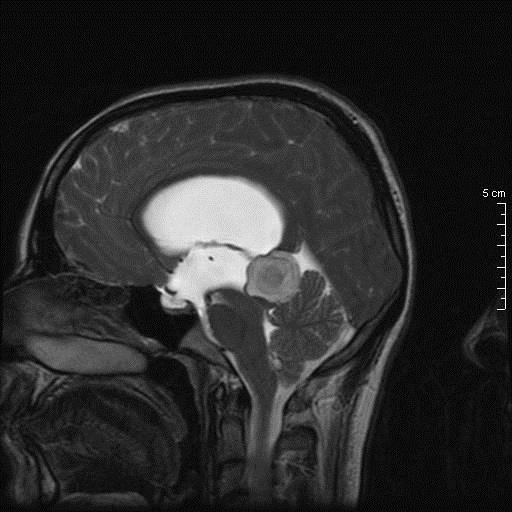

Γυναίκα 34 ετών παρουσιάστηκε με κεφαλαλγία, περιστασιακά διπλωπία και στην εξέταση οίδημα οπτικών θηλών. Η μαγνητική τομογραφία κατέδειξε βλάβη διαμέτρου 26.7 χιλ στην περιοχή της επίφυσης χωρίς ενίσχυση, με πίεση επί του τετραδύμου και σημαντική διάταση του κοιλιακού συστήματος. Σε θέση park bench υποβλήθηκε σε δεξιά πλάγια περιορισμένη ινιακή κρανιοτομία και μέσω της υποσκηνίδιας υπερπαρεγκεφαλιδικής οδού σε ενδοσκοπικά υποβοηθούμενη μακροσκοπικά πλήρη αφαίρεση της βλάβης.

Προεγχειρητικός απεικονιστικός έλεγχος